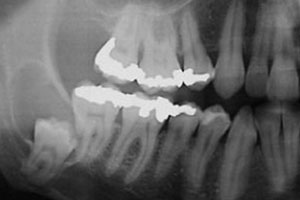

Panoramic radiography revealed a large, well-defined radiolucency surrounding the crown of a deeply impacted right mandibular third molar and involving the distal root of the adjacent second molar (Fig. 1). An initial diagnosis of dentigerous cyst was made (histopathologic examination would be necessary for a conclusive diagnosis). The impacted tooth was in a vertical position, with its root apices in close proximity to the inferior border of the mandible and its crown’s mesial cusp lying lateral and close to the distal root of the adjacent second molar. Computed tomography confirmed a close anatomical relationship between the molar roots and the mandibular canal, as well as between the cyst and the mandibular canal (Fig. 2).

Figure 1: Initial panoramic radiograph shows deep impaction of the right mandibular third molar and a large, well-defined radiolucency surrounding its crown and involving the distal root of the adjacent second molar.

In addition, a small amount of bone seemed to be present at the distal surface of the right mandibular second molar and this raised concern about the long-term periodontal prognosis for this tooth. Clinical evaluation revealed a probing pocket depth of 9 mm on the lingual side and 7 mm on the buccal side of distal root surface of the second molar. Crestal bone loss was also estimated from the radiograph; the distance from the cementoenamel junction to the bottom of the bone defect was 16 mm, confirming its severity.